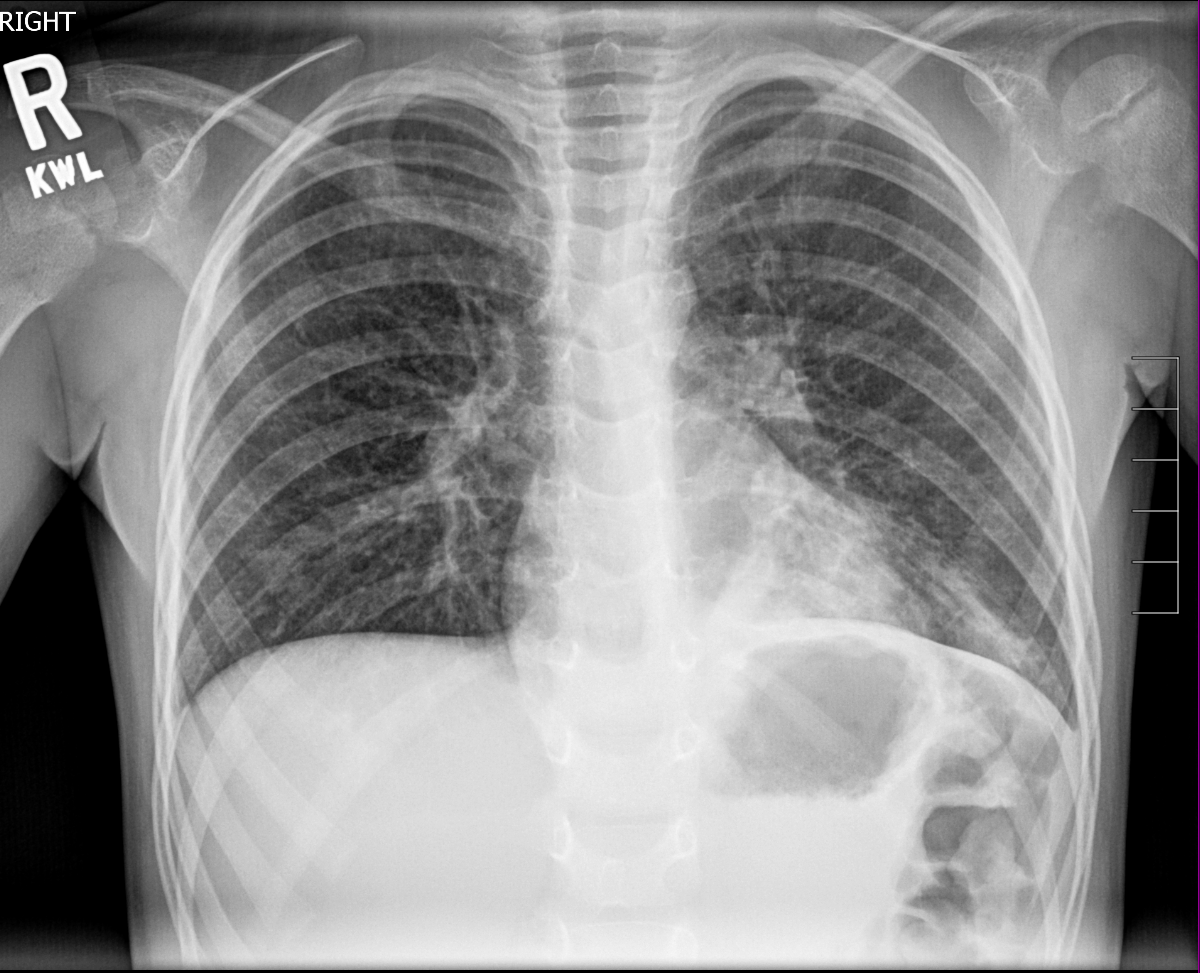

Findings

Soft Tissues

Bone